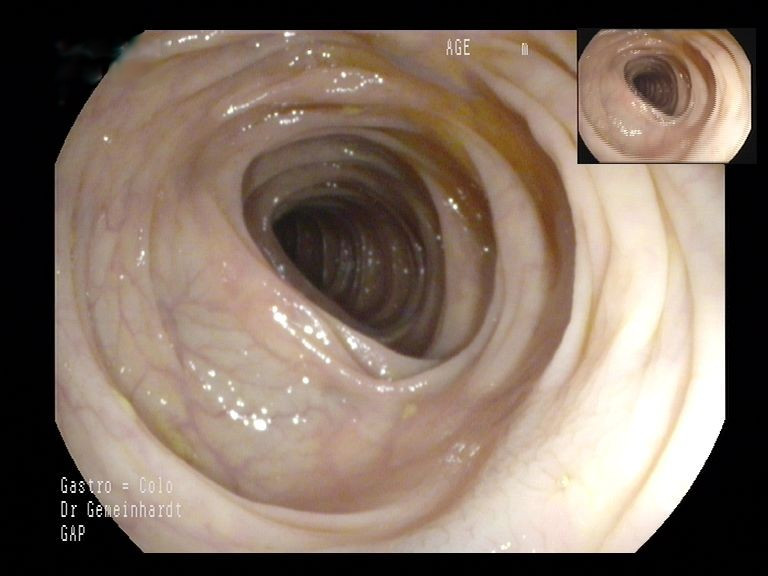

Im Rahmen der Koloskopie werden der gesamte Dickdarm sowie das Ende des Dünndarms (terminales Ileum) untersucht. Die Untersuchung wird in der Regel unter Sedierung durchgeführt, sodass der Patient keinerlei Schmerzen verspürt. Meist liegt die Untersuchungszeit bei unter 20 Minuten. Zum Einsatz kommen nur Geräte der neuesten Generation, die über höchste Bildqualität (HD, virtuelle Chromoendoskopie, künstliche Intelligenz) verfügen.

Darüber hinaus besteht die Möglichkeit, dass die Untersuchung mit Unterstützung durch künstliche Intelligenz (KI) durchgeführt wird. Die KI ersetzt dabei nicht den Untersucher, sondern unterstützt ihn, quasi wie eine "zweites digitales Augenpaar" bei der Suche nach Polypen. Während der Untersuchung wird das Live-Bild permanent mit einer riesigen, ständig wachsenden Datenbank verglichen und auf suspekte Befunde gescreent. Wird ein suspekter Befund entdeckt, wird der Untersucher optisch und akkustisch darauf hingewiesen und kann sich die Stelle gezielt ansehen und diese wenn nötig entfernen. Mehrere Studien konnten inzwischen zeigen, dass die Adenomdetektionsrate (ADR) als maßgebliches Maß der Untersuchungsqualität signifikant gesteigert werden kann, woraus eine höhere Untersuchungsqualität für Sie als Patient resultiert.